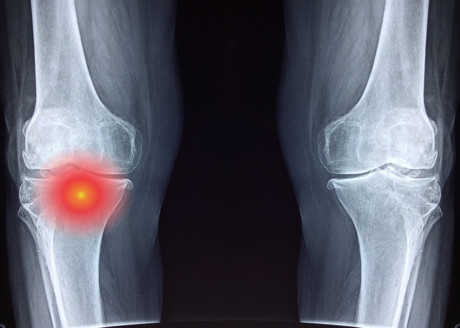

Up to 90% of men with treatment-resistant prostate cancer develop metastases in their bones, from which most of these men will die. While some treatments enhance quality of life and delay the onset of skeletal symptoms in men with bone metastases, they have failed to increase survival. Now, it turns out the immune system could be instrumental in offering an effective treatment approach for prostate cancer bone metastases.

When researchers treated mice bearing metastatic prostate cancer cells with a selective HDAC inhibitor, Entinostat, they found that they could achieve re-expression of IFN inside the cancer cells, decrease the outgrowth of bone metastases and extend survival. The treatment also triggered the activation of specific tumour-killing T immune cells and, when combined with an immune-activator, they were able to completely eliminate bone metastasis. The combination also reduced the activity of certain cells within the bone that can cause bone breakdown.